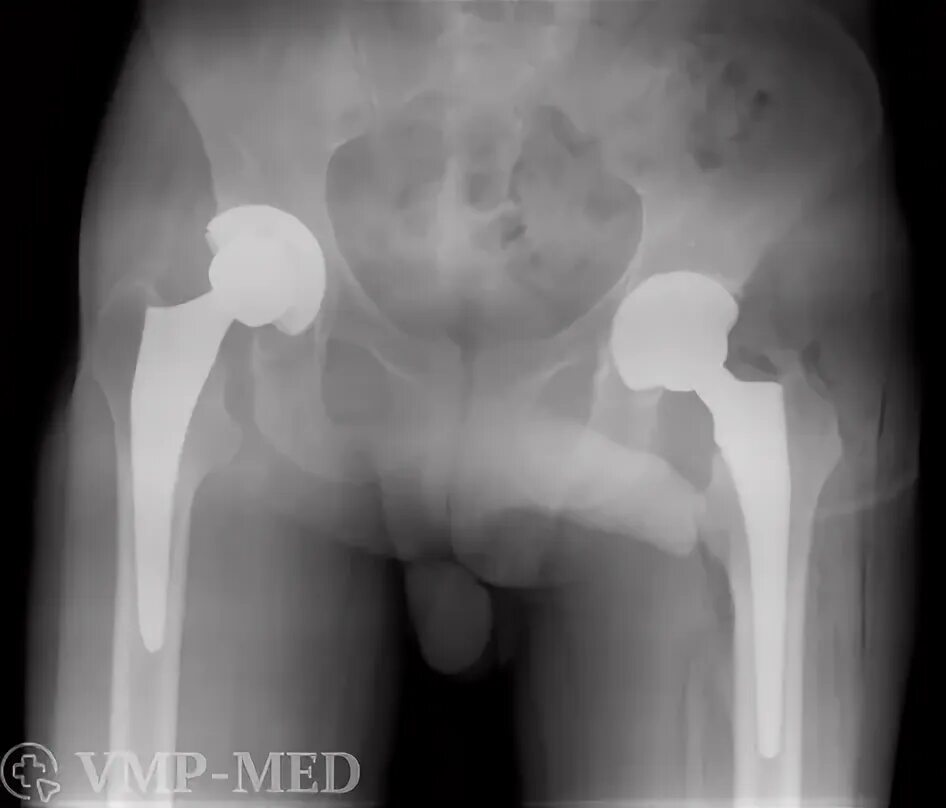

Хобл 1 группа инвалидности. инвалидность 2 группы хобл. хобл группа инвалидности. 2 группа инвалидности при хобл.Инвалидность при артрозе 3 степениГонартроз наколенник коленного. гонартроз 3 степени ортез. бандаж на коленный сустав при артрозе 2 степени.2 группа инвалидности. 3 группа инвалидности. инвалидность группы и степени. 2 группа 3 степень инвалидности.Группы инвалидности по степени трудоспособности. степени инвалидности 3 группы. 2 группа 3 степень инвалидности. инвалидность 1 и 2 степени.Инвалидность при артрозе 3 степениИнвалидность при гонартрозе. нетрудоспособность при остеоартрозе. инвалидизация при артрозе. остеоартроз инвалидность.Коксартроз тазобедренного сустава 2 степени инвалидность. инвалидность 3 степени при коксартрозе тазобедренного. инвалидность при коксартрозе тазобедренного сустава.Инвалидность при артрозе 3 степениГонартроз инвалидность. инвалидизация при артрозе. остеоартроз инвалидность.Коксартроз тазобедренного диагноз. коксартроз тазобедренного сустава инвалидность. коксартроз 2 степени тазобедренного сустава дают ли инвалидность. коксартроз 3 степени тазобедренного сустава инвалидность.Инвалидность при артрозе 3 степениИнвалидность остеоартрит. инвалидизация при артрозе.Инвалидность заболевания. группы инвалидности заболевания. инвалидность по общим болезням. инвалидность заболевания по группам.Инвалидность при артрозе 3 степениГонартроз коленного сустава 2. гонартроз коленного сустава 3. гонартроз 3 степени рентген.1 группа б инвалидности. сетка инвалидности. меланома первая группа инвалидности. инвалидность при трахеостоме.2 группа 3 степень инвалидности. инвалидности 1 2 3 группы пример. категории болезней для инвалидности 1 группы. инвалид 2 группы 3 степени.Инвалидность при гонартрозе. инвалидность при гонартрозе 3 степени.Гипертоническая болезнь 3 риск 4 инвалидность. 3 стадия гипертонии группа инвалидности. гипертоническая болезнь 3 стадии 1 степени риск 4 группа инвалидности. гипертоническая болезнь 2 стадия 2 степени группа риска 3.Группы инвалидности. получение инвалидности. инвалидность группы инвалидности. 2 группа инвалидности это какие заболевания.Коксартроз тазобедренного сустава 3. коксартроз эндопротезирование тазобедренного сустава. диспластический коксартроз тазобедренного сустава. коксартроз тазобедренного сустава 2 степени инвалидность.Инвалидность при артрозе 3 степениМедико-социальную экспертизу для получения инвалидности. мсэ 1 группа инвалидности. медико-социальная экспертиза (мсэ): инвалид, инвалидность. справка об инвалидности ребенка инвалид детства.Коксартроз 2 степени тазобедренного. остеонекроз тазобедренного сустава 2 -3 степени. асептический некроз бедренных костей. коксартроз асептический некроз головки.Инвалидность 2 группы онкология. вторая группа инвалидности по онкологии. 1 группа инвалидности по онкологии. инвалидностью ii группы.2 группа 3 степень инвалидности. инвалидность 2\2 гр. группа инвалидности льготы. 1 группа инвалидности.Инвалидность при артрозе 3 степениАртроз тазобедренного сустава 3 степени положена ли инвалидность. коксартроз 3 степени тазобедренного сустава сняли инвалидность. коксартроз эндопротезирование. коксартроз после эндопротезирования диагноз.Инвалидность при артрозе 3 степениИнвалидность при артрозе 3 степениКоксартроз тазобедренного сустава инвалидность. коксартроз тазобедренного 4 степени инвалидность. инвалидность 3 степени при коксартрозе тазобедренного. коксартроз тазобедренного сустава 2 степени инвалидность.Инвалидность при артрозе 3 степениИнвалидность при артрозе 3 степениМедико-социальная экспертиза (мсэ): инвалид, инвалидность. втэк 3 группа инвалидности. 2 группа инвалидности. мсэ 2 группа инвалидности.Диспластический коксартроз рентген. снимки коксартроза 1.2.3 степени тазобедренного сустава. коксартроз 4 степени тазобедренного. диспластический коксартроз тазобедренного сустава рентген.Инвалидность при артрозе 3 степениИнвалидность при артрозе 3 степениФункциональные классы нарушения функции суставов. степени функциональной недостаточности суставов. степени нарушения функции суставов. функциональное нарушение суставов классификация.Группы инвалидности. вторая группа инвалидности. легкая группа инвалидности. дают ли инвалидность.Получение группы инвалидности. инвалидность по группам. заболевания по инвалидности. сроки получения инвалидности.Инвалидность при артрозе 3 степениИнвалидность при артрозе 3 степениИнвалидность при артрозе 3 степениИнвалидность при артрозе 3 степениСтенокардия формулировка диагноза. инвалидность при ибс. инвалидность заболевания по группам. группа инвалидности при стенокардии.Справка об инвалидности. мсэ и инвалидность по зрению. 2 группа инвалидности. 3 группа инвалидности.Инвалидность при артрозе 3 степениИнвалидность 2 группы онкология. группа инвалидности при болезни. 1 группа инвалидности. группы инвалидности при онкологии группы.Инвалидность при артрозе 3 степениВторая группа инвалидности бессрочно. справка об инвалидности бессрочно. 3 группа инвалидности бессрочно. бессрочная инвалидность 2 группы.Продольное плоскостопие 1. продольно-поперечное плоскостопие 2 степени. продольным или поперечным плоскостопием ii степени. продольное плоскостопие деформация стопы.1 2 3 группа инвалидности. инвалидность группы и степени. степень инвалидности по группам. критерии присвоения группы инвалидности.Первичный гонартроз двусторонний. гонартроз коленного сустава. деформирующий артроз 2. деформирующий артроз 1-2 степени.Инвалидность при артрозе 3 степениПеречень заболеваний для инвалидности. инвалидность 2 группы перечень заболеваний. вторая группа инвалидности болезни. инвалидность 1 и 2 группы перечень заболеваний.Втэк 3 группа инвалидности. форма справки мсэ по инвалидности. мсэк бессрочная инвалидность 2 группы. справка мсэ об инвалидности 1 группы.Справка об инвалидности 3 группы. инвалидность группы инвалидности. вторая группа инвалидности. группа инвалидности бессрочно.Инвалидность при артрозе 3 степениИнвалидность при артрозе 3 степениСтепень инвалидности при остеохондрозе. инвалидность при 3 степени остеохондроза. полагается ли группа инвалидности при заболеваниях позвоночника?. инвалидность по сколиозу 3.Группы инвалидности. третья группа инвалидности. инвалидность по группам. вторая группа инвалидности.Дают ли при инфаркте 3 группу инвалидности. инфаркт миокарда инвалидность. положена ли инвалидность после инфаркта миокарда и стентирования. инвалидность по инфаркту миокарда.Группы инвалидности. степени инвалидности. инвалидность группы и степени. 1 группа инвалидности.Инвалидность при артрозе 3 степениИнвалидность при артрозе 3 степениИнвалидность при артрозе 3 степениИнвалидность при переломе бедра. отсутствие конечности группа инвалидности. группа инвалидности при ампутации голени. группы инвалидности ампутация.Инвалидность группы инвалидности. группа инвалидности при болезни. диагнозы инвалидов. f70 диагноз инвалидность.Инвалидность при артрозе 3 степени